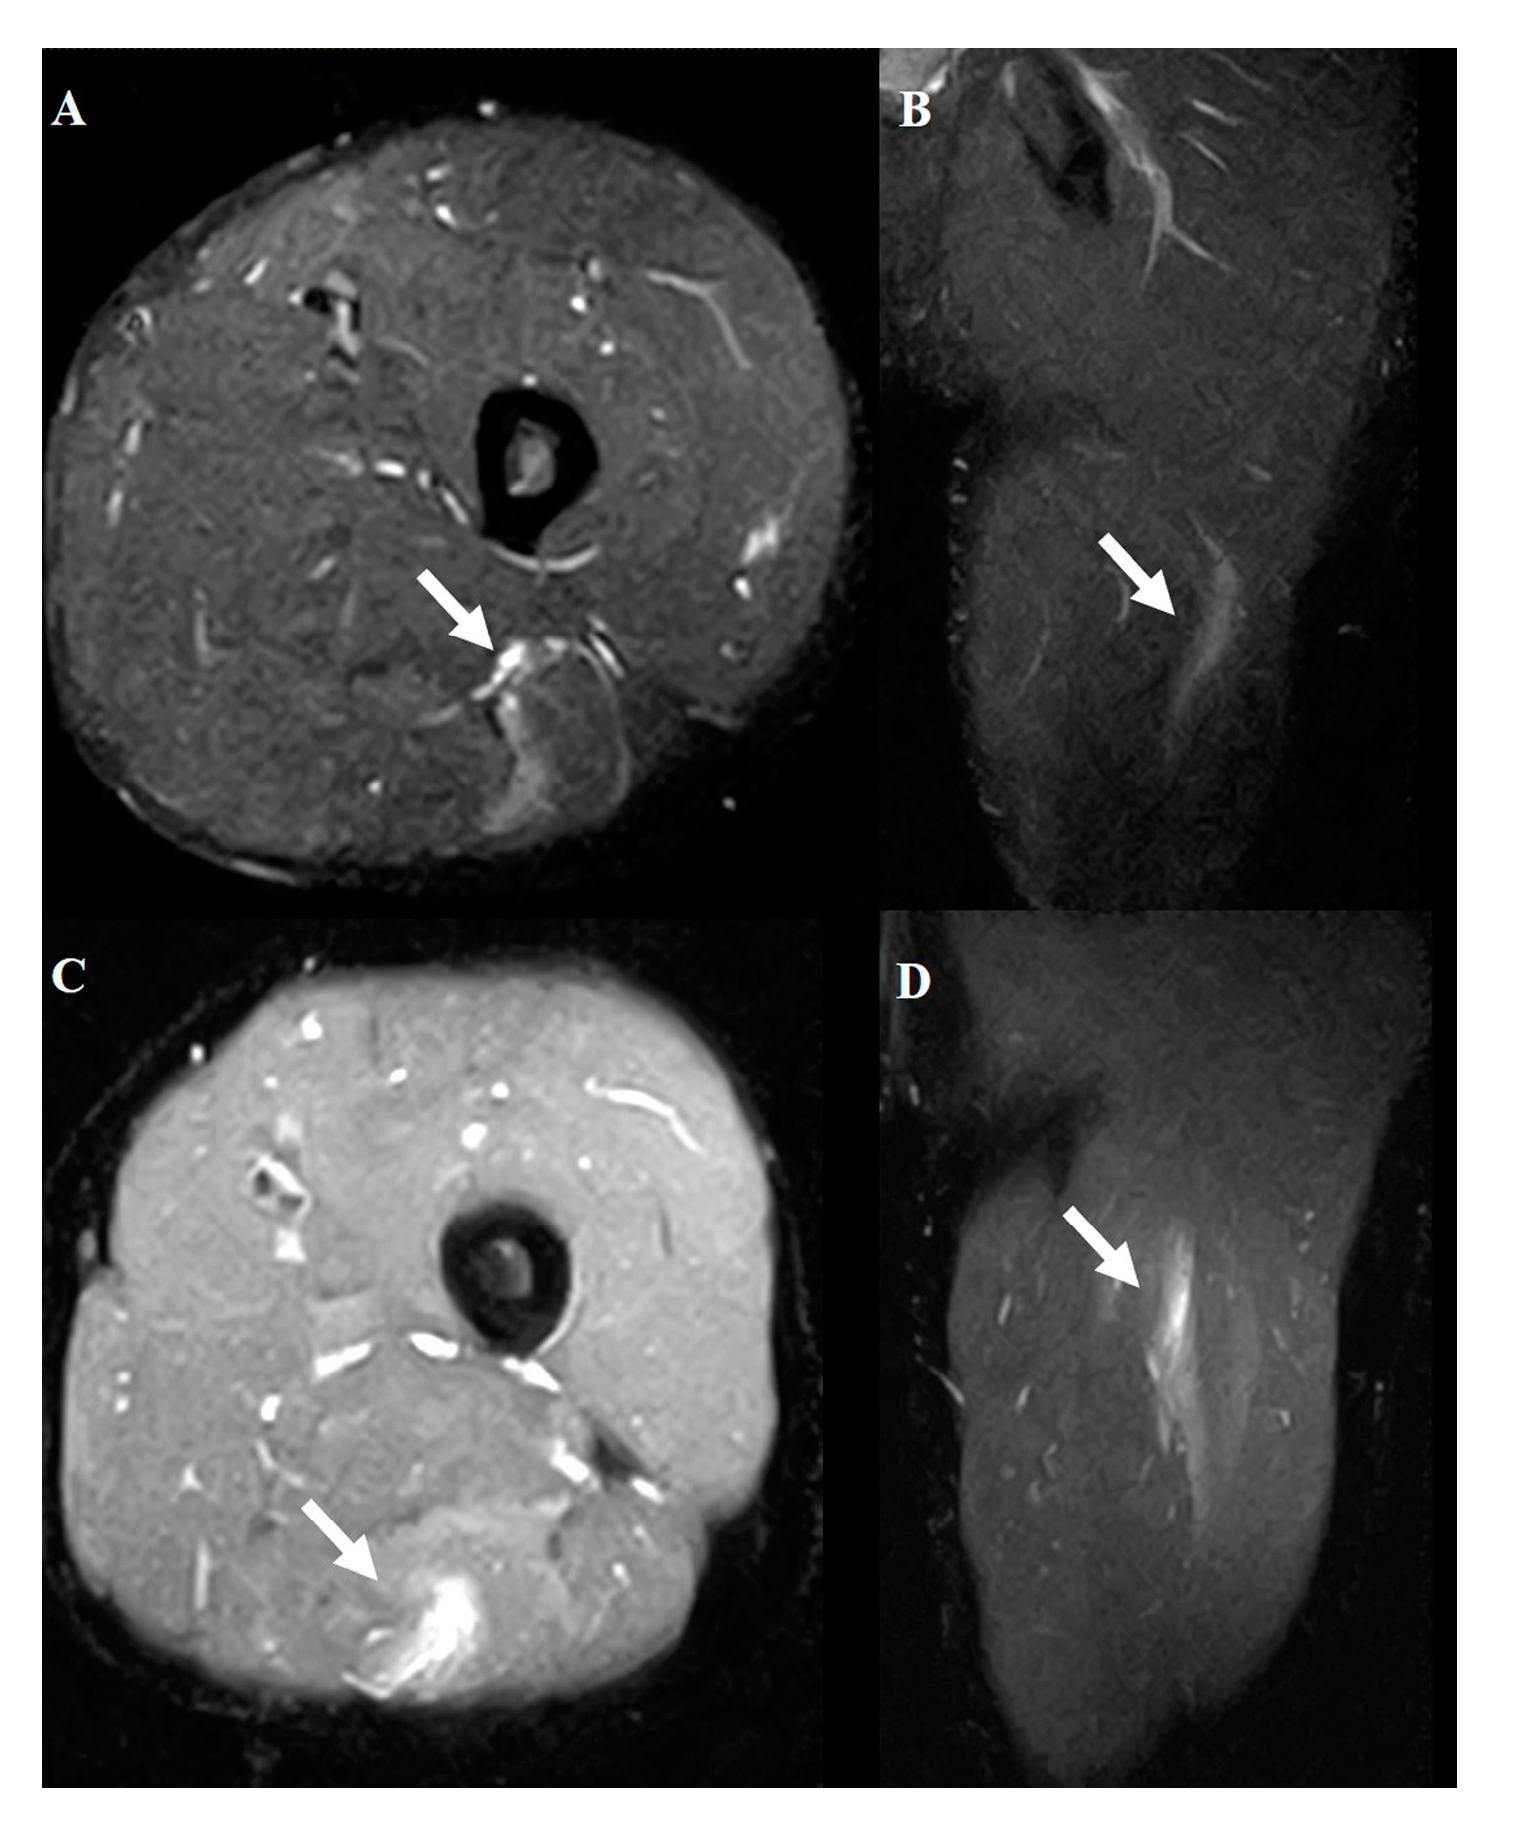

Figure 3. Typical MRI findings in tendon injury. Axial (A) and coronal (B) views of grade 1. Axial (C) and coronal (D) views of grade 2. Axial (E) and coronal (F) views of grade 3. The white arrows indicate the injured area.